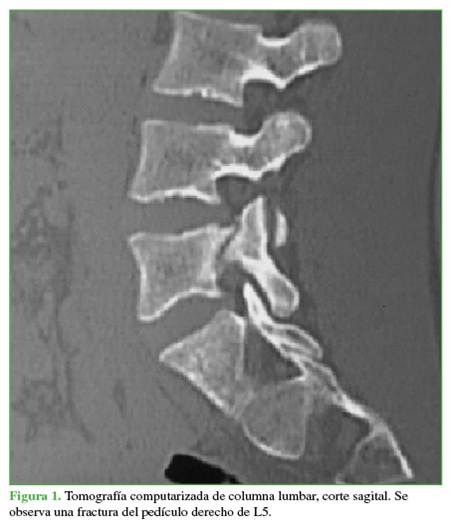

Se tomaron radiografías de columna lumbar, de frente, de perfil y oblicuas que revelaron esclerosis del pedículo derecho y espondilólisis izquierda de L5. La tomografía computarizada mostró, además de la lesión antes descrita, una solución de continuidad en el pedículo derecho, con márgenes escleróticos e hipertróficos (Figuras 1 y 2). En la resonancia magnética, se visualizó un edema en dicho pedículo lumbar (Figuras 3 y 4).

Un rasgo habitual en la pediculólisis es la esclerosis del pedículo, pero aún no resulta claro si esto representa un fenómeno de adaptación anterior a la fractura o si es una consecuencia de ella.9 Esta esclerosis unilateral le da el aspecto de vértebra anisocórica en la imagen radiológica. Sin dudas, la tomografía computarizada permite evaluar mejor el cuadro, realizar diagnósticos diferenciales, controlar la evolución y, en algunos casos, efectuar una planificación terapéutica. Las características suelen ser la presencia de solución de continuidad radiolúcida con márgenes escleróticos e hipertróficos.4 La resonancia magnética tiene una elevada sensibilidad a la hora de diagnosticar este tipo de lesiones que, si bien puede mostrar o no el trazo de fractura a nivel del pedículo, sí manifiesta el edema

como una imagen hipointensa en la secuencia T1 e hiperintensa en la secuencia T2.3,4